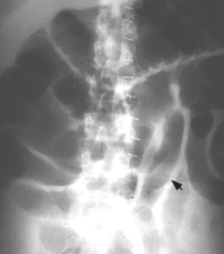

A patient presents with crampy abdominal pain associated with bilious vomiting, abdominal distension and constipation. They have had previous abdominal surgery

SBO

Causes: adhesions from previous surgery, inguinal hernia with incarceration, Crohn’s disease, malignancy, appendicitis